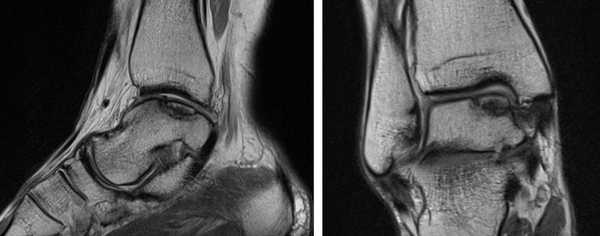

а. схематическое изображение рассекающего остеохондрита таранной кости. б. на МРТ и рентгенограммах определяется рассекающий остеохондрит.

На МРТ выявляется рассекающий остеохондрит с отделением костно-хрящевого фрагмента от таранной кости.

МРТ является ценным инструментом в комплексе диагностики ОХПТК для оценки отека костной ткани, а также выявления скрытых повреждений субхондральной кости и хрящевого покрытия, которые могут быть пропущены при стандартных рентгенограммах или даже КТ. МРТ – самый лучший инструмент оценки для определения стабильности и жизнеспособности фрагмента таранной кости при его отслоении и эта информация может быть решающей в тактике выбора того или иного метода хирургического лечения. Однако, для определения размеров отслоившегося фрагмента таранной кости наилучший метод КТ, так как данные размеров по МРТ могут не соответствовать действительности в сторону переоценки последних. Hepple с соавторами изучив многочисленные данные МРТ диагностики разработали систему классификации ОХПТК на основе этого метода (Табл. 2) [23]. Однако, наиболее широко принятая система классификации, основанная на КТ-это классификация Ferkel и Sgalione (Табл. 3; Рисунок 4) [24]. Классифицировать ОХПТК также возможно выполнить интраоперационно, на основе артроскопических данных о состоянии остеохондрального поражения. Наиболее широко используется система Ferkel/Cheng (Табл. 4) [25], эта система классификации, в отличие от обычных рентгенограмм, КТ и МРТ, лучше всего взаимосвязана с исходами лечения пациентов.